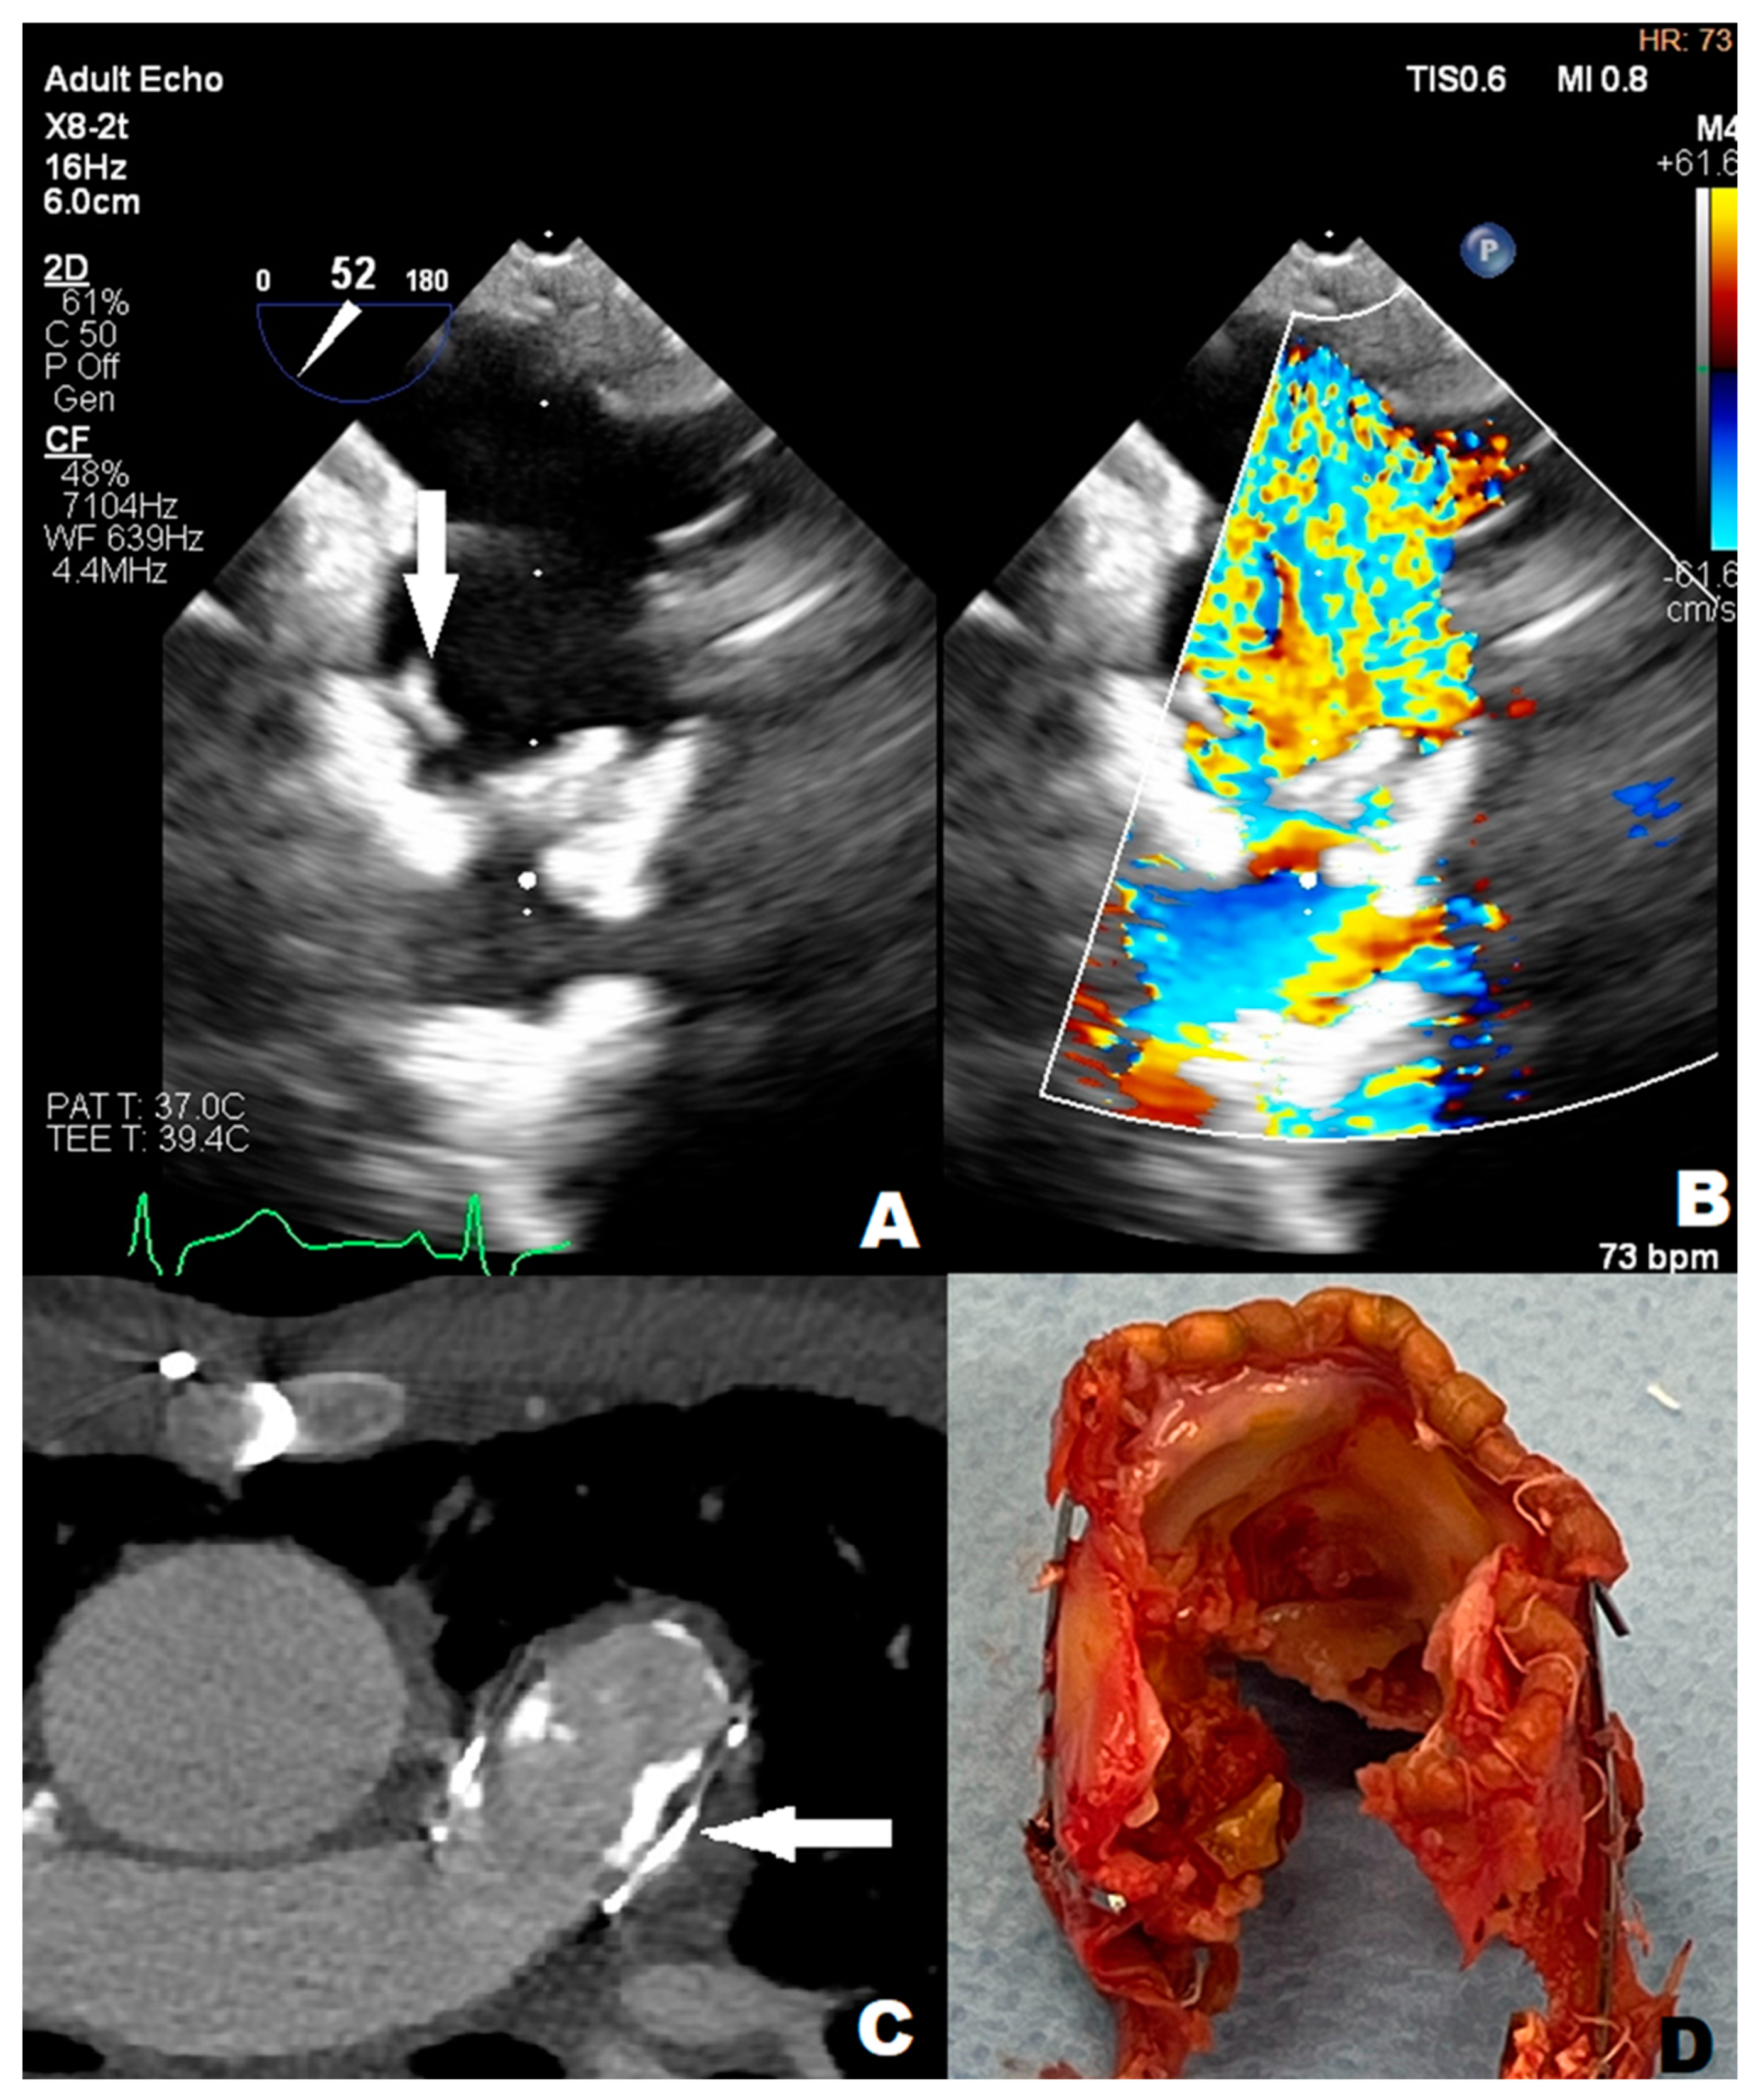

3.1. Case 1